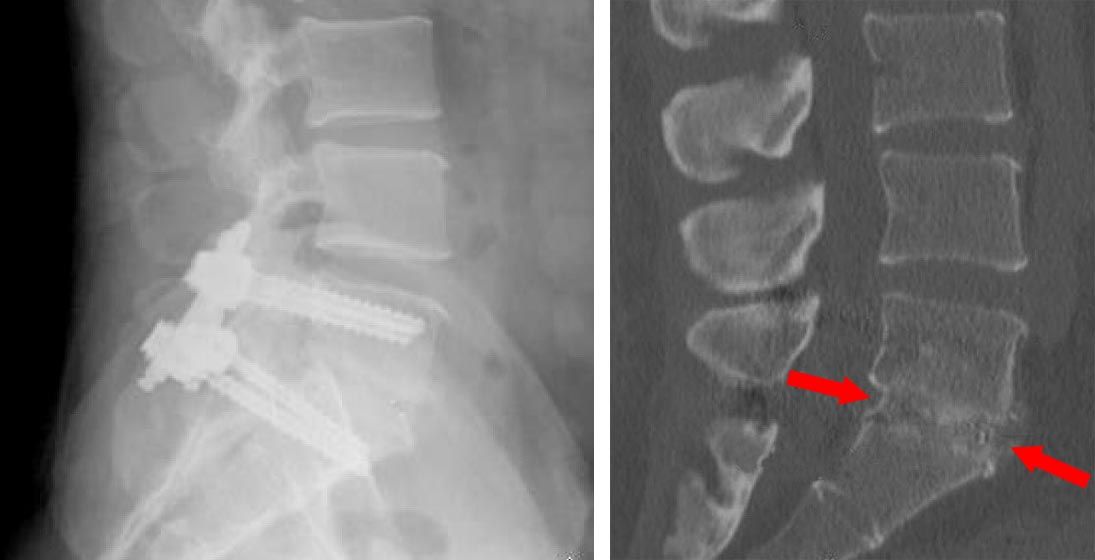

X-ray of TLIF procedure and CT scan of fusion

(Left) An X-ray of a TLIF procedure. (Right) A CT scan of the same patient showing the healed fusion. Note that bone has grown through the cage, so the cage is not visible. The screws and rods used to stabilize the spine are still in place but cannot be seen from this angle.